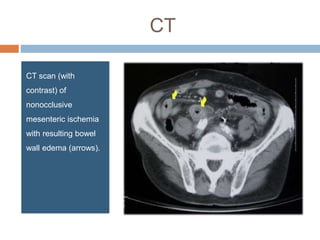

CT

CT scan (with

contrast) of

nonocclusive

mesenteric ischemia

with resulting bowel

wall edema (arrows).

CT CT scan (with contrast)of nonocclusive mesenteric ischemia with resulting bowel wall edema (arrows).